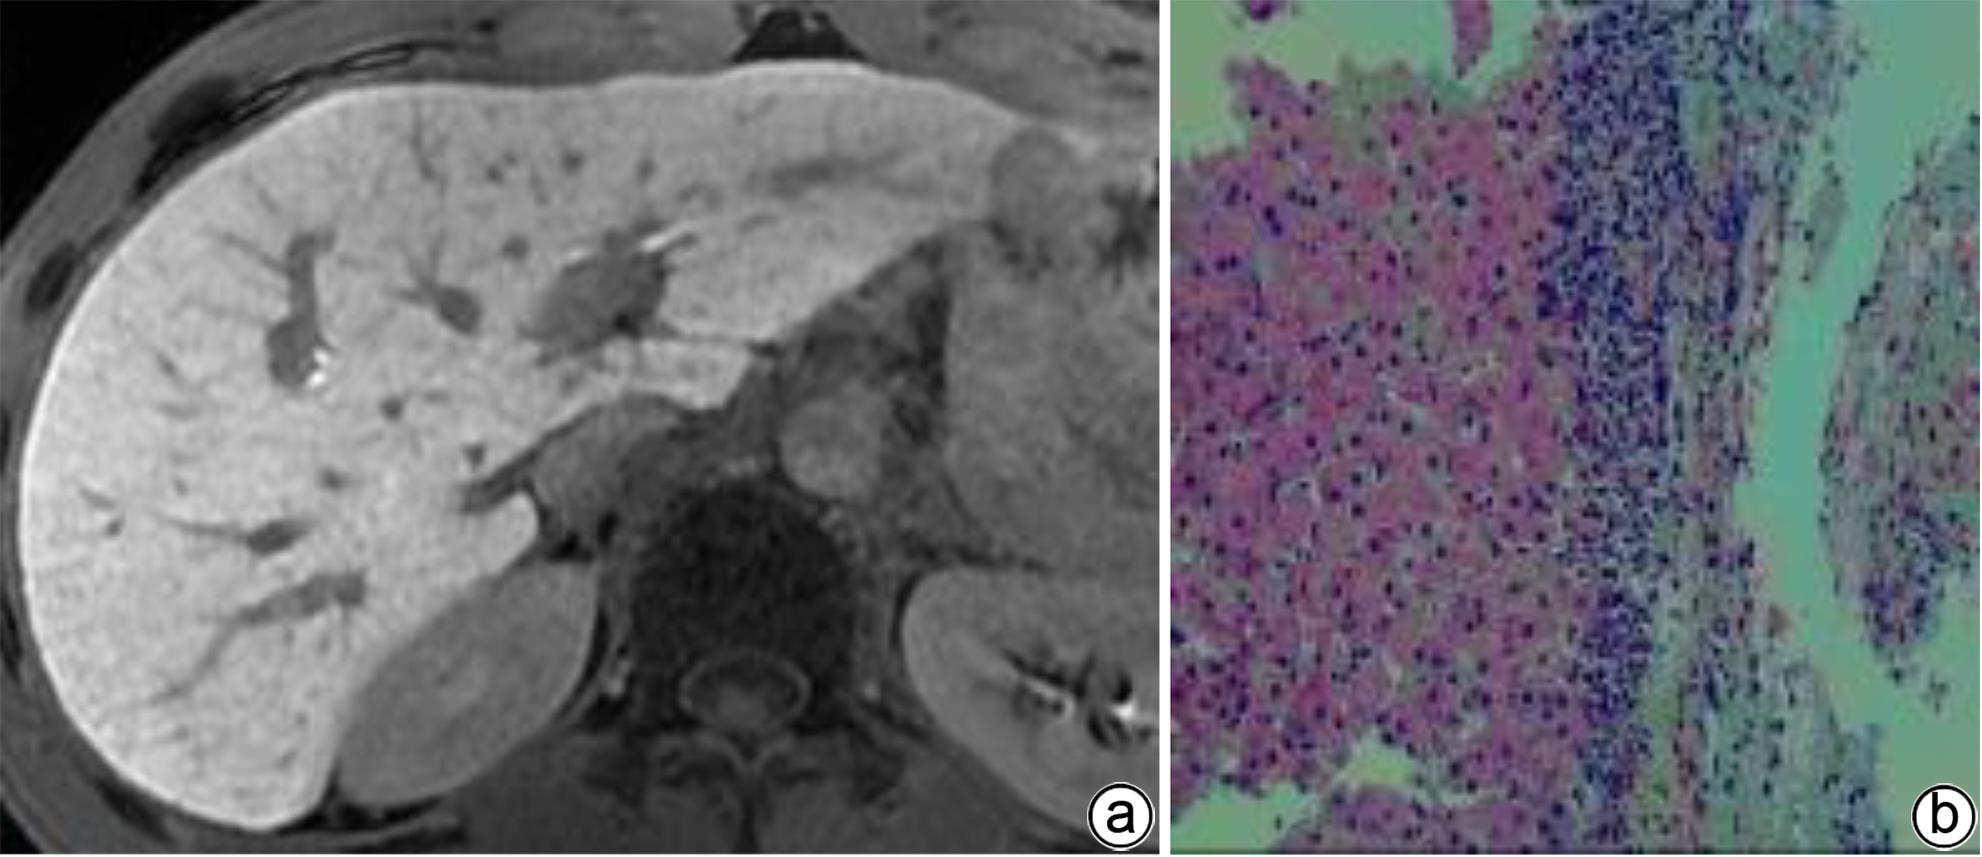

Efficacy of endoscopic ultrasound-guided coil placement combined with tissue adhesive injection in treatment of gastric varices with spontaneous shunt

Yafen TANG, Zhiyang JIANG, Dan LONG, Jinmin CHEN, Shan GAO

2024, 40(4): 739-744. DOI: 10.12449/JCH240416

Abstract(1096) HTML (592) PDF (917KB)(78)

Abstract:

Objective  To investigate the efficacy, safety, and cost-effectiveness of endoscopic ultrasound (EUS)-guided coil placement combined with tissue adhesive injection in the treatment of gastric varices with spontaneous shunt.  Methods  A retrospective analysis was performed for the patients with acute gastric variceal bleeding and spontaneous portosystemic shunt who were hospitalized and received balloon-occluded retrograde transvenous obliteration (BRTO) combined with endoscopic tissue adhesive injection or EUS-guided coil placement combined with tissue adhesive injection in Xiangyang Central Hospital from March 2019 to September 2022. The two surgical procedures were compared in terms of efficacy (technical success rate, 5-day rebleeding rate, 1-year rebleeding rate, and time to rebleeding), safety (the incidence rate of ectopic embolism, the amount of tissue adhesive used, and the amount of lauromacrogol used), and cost-effectiveness (hospital costs and length of hospital stay). The t-test was used for comparison of normally distributed continuous data between two groups, and the Mann-Whitney U test was used for comparison of non-normally distributed continuous data between two groups. The Kaplan-Meier method was used to estimate the rebleeding. The chi-square test was used for comparison of categorical data between two groups.  Results  A total of 25 patients received successful EUS-guided coil placement and tissue adhesive injection, with a technical success rate of 100%, a median amount of 2.5 mL tissue adhesive used, a median amount of 11.0 mL lauromacrogol used, a mean length of hospital stay of 14.88±3.21 days, a mean hospital cost of 32 660.00±4 602.07 yuan, and a 5-day rebleeding rate of 0%; among these patients, 2 were lost to follow-up, and 23 patients with complete follow-up data had an incidence rate of ectopic embolism of 0% and a median time to rebleeding of 689 days. A total of 14 patients underwent modified BRTO combined with endoscopic tissue adhesive injection, with a technical success rate of 100%; a median amount of 5.0 mL tissue adhesive used during surgery, which was significantly higher than that used in EUS (U=39.000, P<0.001); a median amount of 10.5 mL lauromacrogol used during surgery; a mean length of hospital stay of 15.38±4.94 days; a mean hospital cost of 57 583.47±18 955.40 yuan, which was significantly higher than that used in EUS (t=-6.310, P<0.001); a 5-day rebleeding rate of 0%. No patient was lost to follow-up, and all 14 patients had an incidence rate of ectopic embolism of 0% and a median time to rebleeding of 244.50 days, with no significant difference between the two groups (χ2=1.448, P=0.229).  Conclusion  EUS-guided coil placement combined with tissue adhesive injection is a relatively safe and effective technique for the treatment of gastric variceal bleeding and has a high technical success rate, a low incidence rate of serious adverse events, and similar efficacy to BRTO, with higher safety and cost-effectiveness.